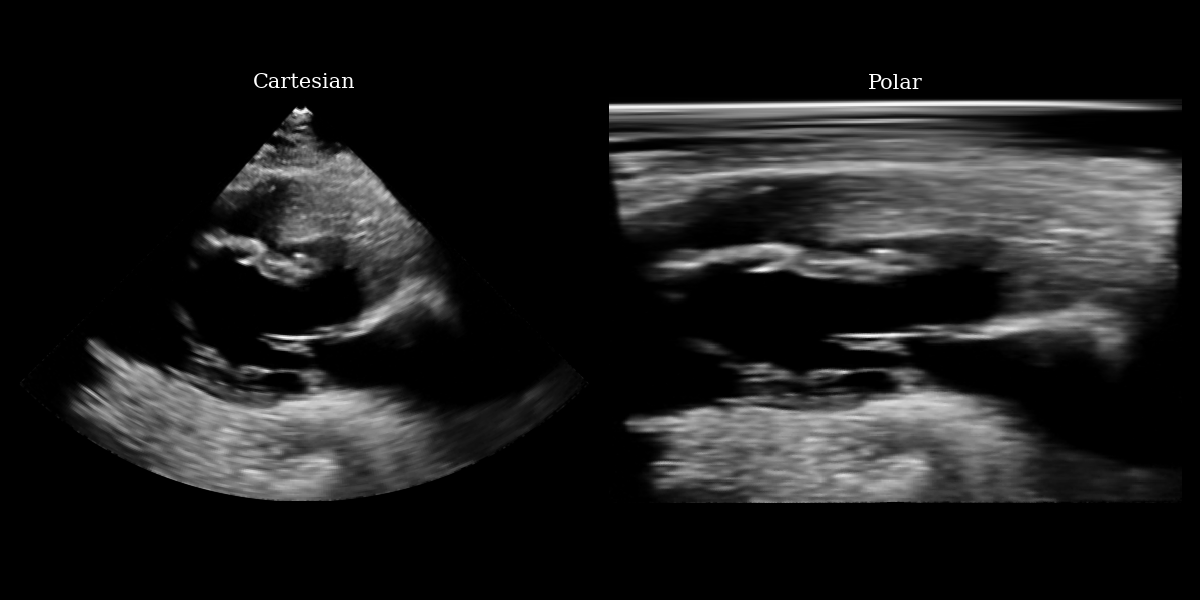

# NOTE: this is a synthetic PLAX view image generated by a diffusion model.

fig, (ax1, ax2) = plt.subplots(1, 2, figsize=(12, 6))

ax1.imshow(img_np, cmap="gray")

ax1.set_title("Cartesian", fontsize=15)

ax1.axis("off")

ax2.imshow(img_polar_np, cmap="gray")

ax2.set_title("Polar", fontsize=15)

ax2.axis("off")

plt.tight_layout()

plt.savefig("cartesian_polar.png")

plt.close()

Cartesian Polar input